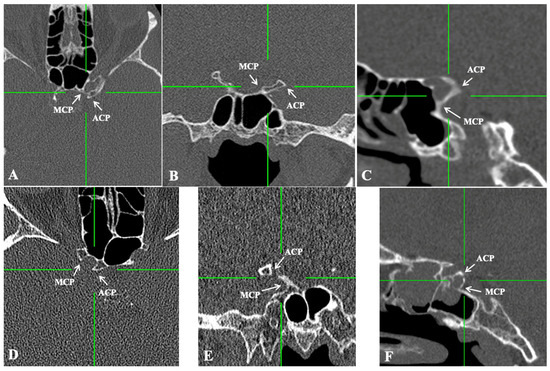

Of the total of 520 sides, the CCB was identified in 89 sides (89/520, 17.1%), unilaterally in 51 skulls (51/260, 19.6%) and bilaterally in 19 skulls (19/260, 7.3%). The CCB was identified in the complete type in 60 sides (60/520, 11.5%) (Figure 2 and Figure 3) and in the incomplete type in 29 sides (29/520, 5.6%) (Figure 2 and Figure 3). The distributions of the sides and sexes are summarized in Table 1. No differences between the sides, sexes, or ages were identified.

Figure 3. The presence of the caroticoclinoid bar (CCB) in computed tomography scans. (AC) Axial, coronal, and sagittal reconstructions of a complete CCB. (DF) Axial, coronal, and sagittal reconstructions of an incomplete CCB. ACP—anterior clinoid process; MCP—middle clinoid process.